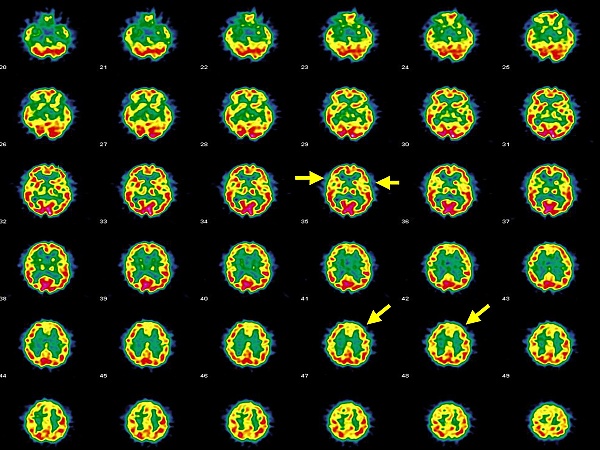

Патологические изменения при магнитно-резонансной томографии включают ишемические поражения, демиелинизацию, отёк, атрофию, а также патологические сигналы в гиппокампе или височной доле[1].